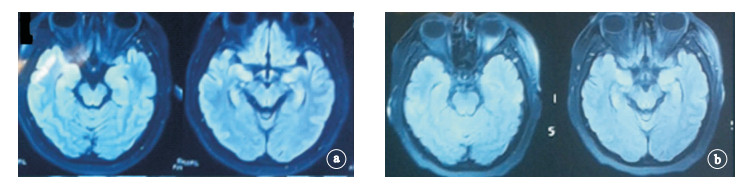

15例患者均行頭部MRI檢查:①抗NMDA受體腦炎異常2例,表現為雙側海馬異常者1例(例4),經免疫治療后復查明顯好轉(圖 4);額葉腦回異常信號1例。②LGI1受體腦炎異常4例,主要表現為顳葉內側、海馬異常信號,1例同時伴基底節區異常信號(例9),經免疫治療后好轉(圖 5)。③抗Hu抗體腦炎1例右側顳葉、雙側海馬Flair像稍高信號。